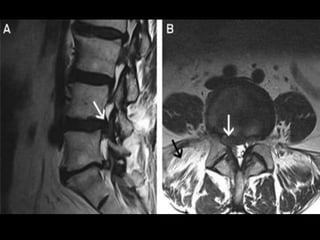

INVESTIGATIONS

MRI

• Clearly superior in the detection of disc

degeneration.

• Allow evaluation of complete spinal group

• Shows:

• Intervertebral disc protrusion.

• Compression of nerve root